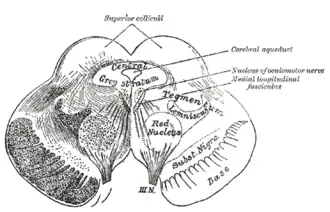

Поперечный разрез среднего мозга. Цифрой 2 показан водопровод мозга

Поперечный разрез среднего мозга. Цифрой 2 показан водопровод мозга Поперечный разрез среднего мозга на уровне нижнего двухолмия.

Поперечный разрез среднего мозга на уровне нижнего двухолмия. Поперечный разрез среднего мозга на уровне верхнего двухолмия.